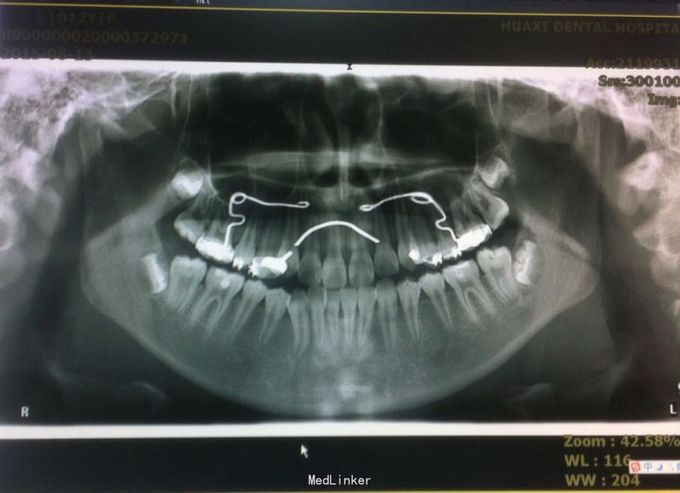

恒牙期 口内见摆式矫治器 左侧磨牙近中关系,右侧中性关系 前牙覆合覆盖正常 中线不正 上下牙列拥挤 张口度正常 关节有弹响 开口型异常

安氏三类 拆除摆式矫治器,清洁牙面,直丝弓矫治器,排齐整平上下牙列,矫治后磨牙中性关系,前牙覆合覆盖正常,维持现有面型

1、在治疗过程中根据面型可能需要片磨上下牙 2、18、28、38、48牙胚存在,必要时拔除